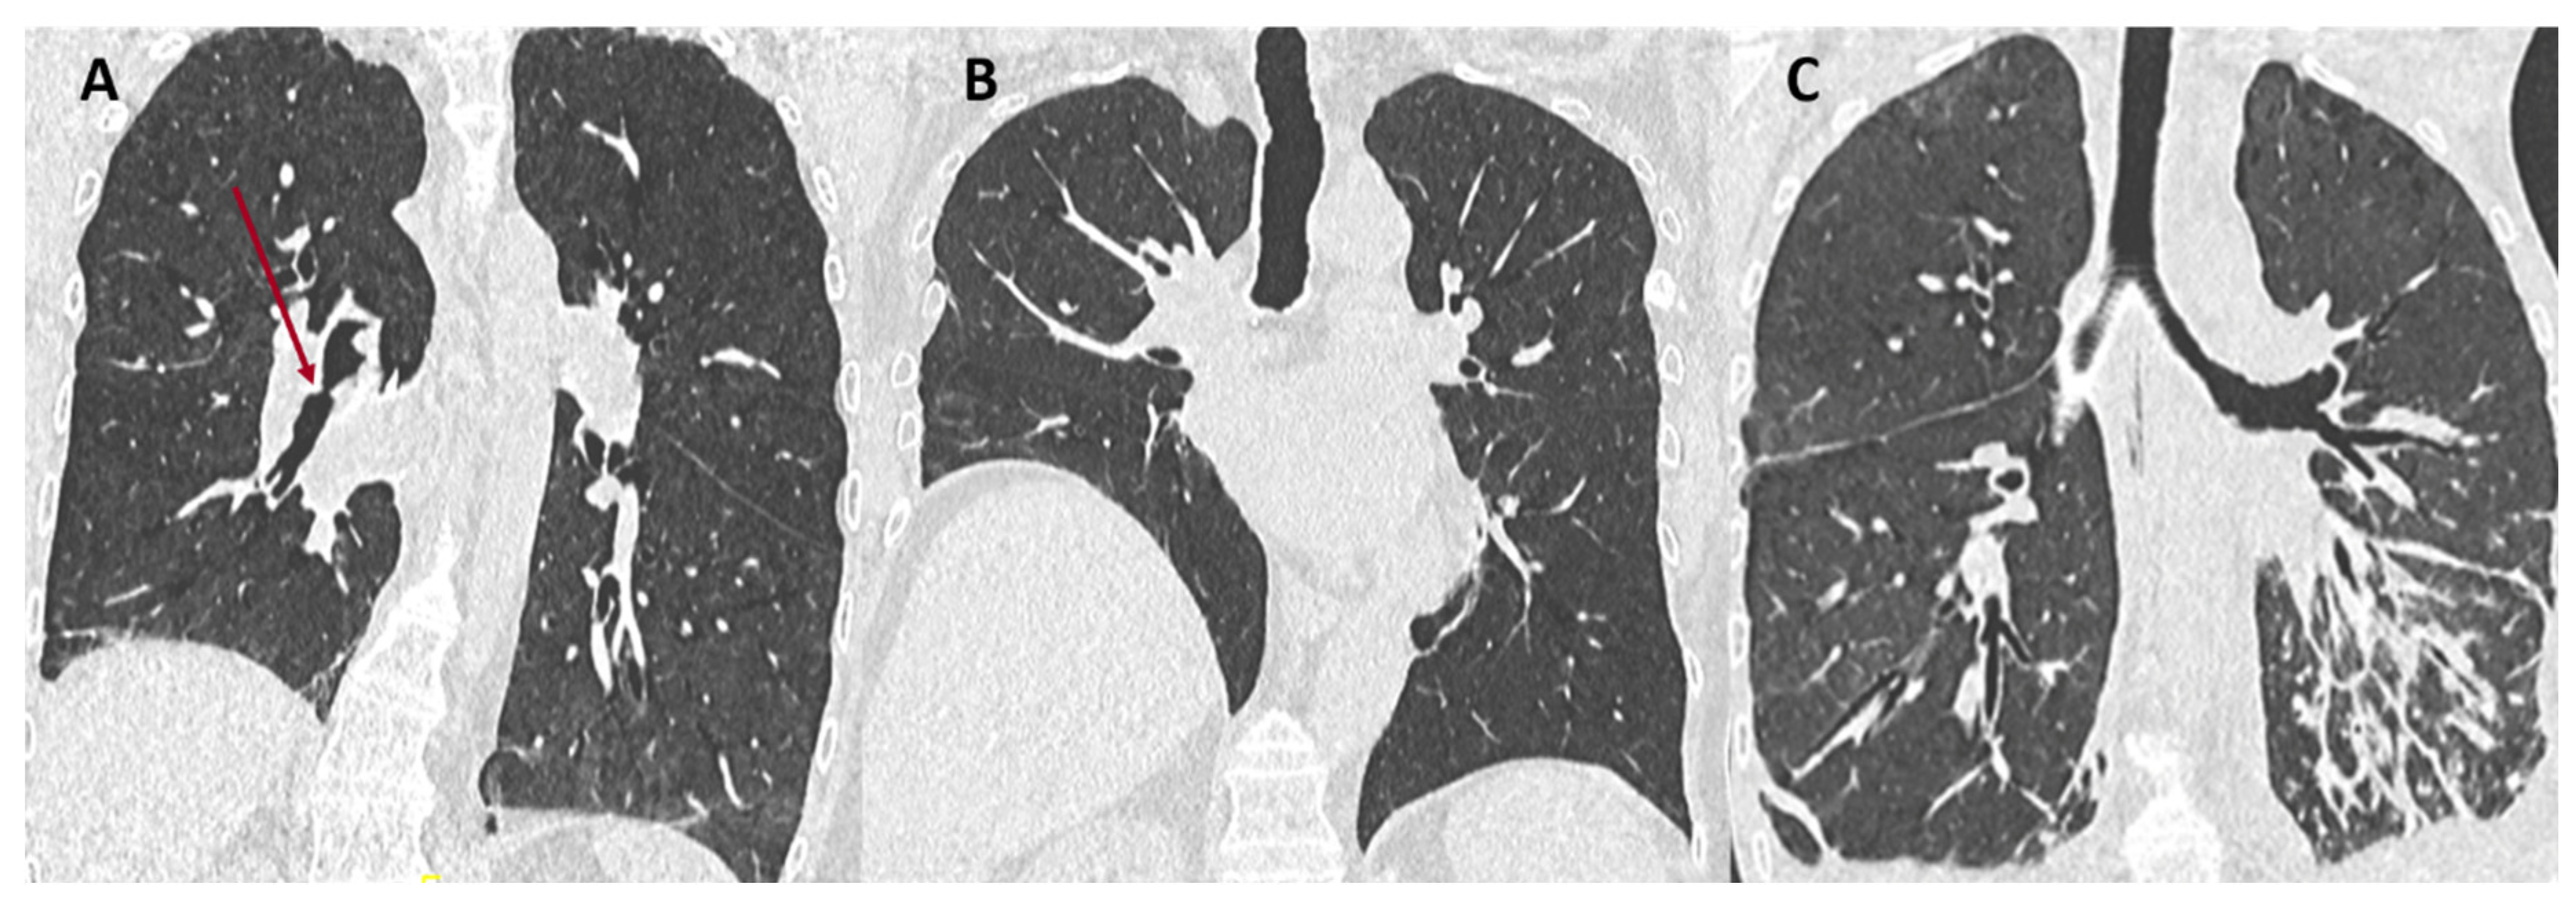

- Dubbeldam, A.; Barthels, C.; Coolen, J.; Verschakelen, J.A.; Verleden, S.E.; Vos, R.; Verleden, G.M.; De Wever, W. Restrictive allograft syndrome after lung transplantation: New radiological insights. Eur. Radiol. 2016, 27, 2810–2817. [Google Scholar] [CrossRef]

- Byrne, D.; Nador, R.G.; English, J.C.; Yee, J.; Levy, R.; Bergeron, C.; Swiston, J.R.; Mets, O.M.; Muller, N.L.; Bilawich, A.-M. Chronic Lung Allograft Dysfunction: Review of CT and Pathologic Findings. Radiol. Cardiothorac. Imaging 2021, 3, e200314. [Google Scholar] [CrossRef] [PubMed]

- Verleden, S.E.; de Jong, P.A.; Ruttens, D.; Vandermeulen, E.; Van Raemdonck, D.E.; Verschakelen, J.; Vanaudenaerde, B.M.; Verleden, G.M.; Vos, R. Functional and computed tomographic evolution and survival of restrictive allograft syndrome after lung transplantation. J. Heart Lung Transplant. 2014, 33, 270–277. [Google Scholar] [CrossRef] [PubMed]

- Glanville, A.R.; Verleden, G.M.; Todd, J.L.; Benden, C.; Calabrese, F.; Gottlieb, J.; Hachem, R.R.; Levine, D.; Meloni, F.; Palmer, S.M.; et al. Chronic lung allograft lung dysfunction: Definition and update of restrictive allograft syndrome. A consensus report from the Pulmonary Council of the ISHLT. J. Heart Lung Transplant. 2019, 38, 483–492. [Google Scholar] [CrossRef]

- Konen, E.; Weisbrod, G.L.; Pakhale, S.; Chung, T.; Paul, N.S.; Hutcheon, M.A. Fibrosis of the Upper Lobes: A Newly Identified Late-Onset Complication After Lung Transplantation? Am. J. Roentgenol. 2003, 181, 1539–1543. [Google Scholar] [CrossRef]

- Verleden, S.E.; Ruttens, D.; Vandermeulen, E.; Bellon, H.; Dubbeldam, A.; De Wever, W.; Dupont, L.J.; Van Raemdonck, D.E.; Vanaudenaerde, B.M.; Verleden, G.M.; et al. Predictors of survival in restrictive chronic lung allograft dysfunction after lung transplanttion. J. Heart Lung Transplant. 2016, 35, 1078–1084. [Google Scholar] [CrossRef]